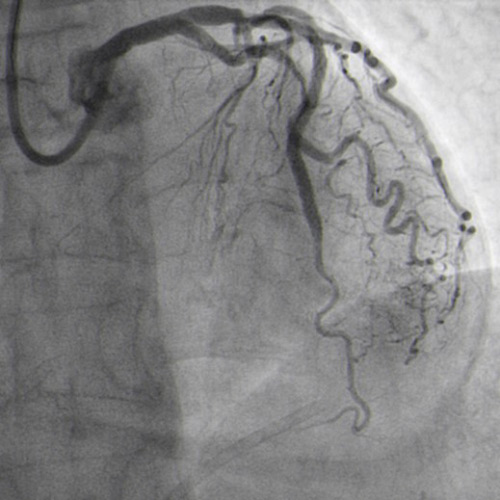

CTO crossed with Miracle 6g, after unsuccessful attempts with Sion and Pilot 150. Floppy wire in diagonal branch to improve support (Figure 4.2).

Guide wires to LAD and diagonal branch (Figure 4.2)